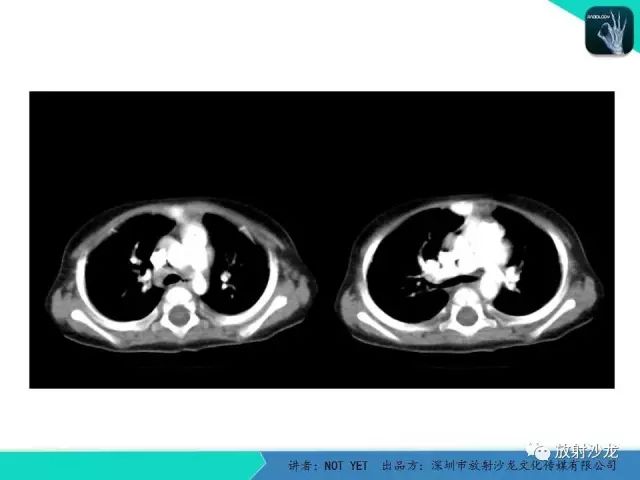

【病例】动脉导管未闭1例CT影像表现